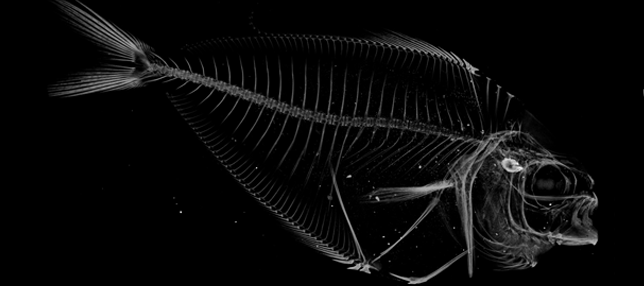

X-ray microscopy (XRM) is a nearly identical imaging modality that combines X-ray imaging with microscope technology to enhance the spatial resolution to 0.7 μm. This unique set-up allows for ex-vivo and nonorganic samples of almost any size or shape to be imaged.

The Micro-Computed Tomography Imaging Core Facility at BU has one μCT scanner and one X-ray microscope. The μCT scanner is a Scanco μCT40 system which is density calibrated on a weekly basis to keep our scans accurate. The XRM is the Zeiss Xradia Versa 520. We have multiple software options that allow for the identification of sub-regions for image segmentation, registration, and quantitative analysis. Analyses can be performed on three-dimensional regions of interest to quantify porosity, thickness, and other features of the microstructure. Additionally, two-dimensional regions of interest can be analyzed to quantify bone area, bone area fraction, cross-section area, and moment of inertia. We have the ability to render and export images in a variety of file formats.